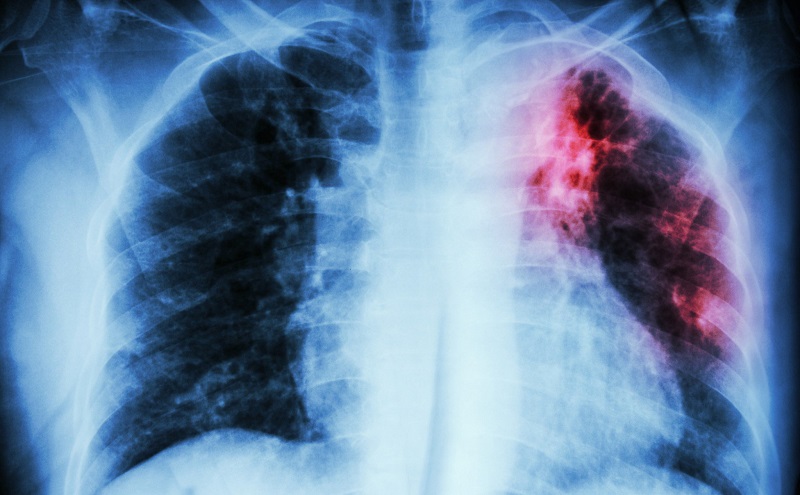

viem phoi ho ra mau Ho ra máu là dấu hiệu nghiêm trọng của bệnh viêm phổi

Bệnh nhân cần được thực hiện các thăm dò chẩn đoán như chụp X-quang phổi, siêu âm, làm xét nghiệm máu để xác định chính xác tình trạng bệnh cũng như tác nhân gây bệnh để đưa ra phác đồ điều trị hiệu quả nhất.